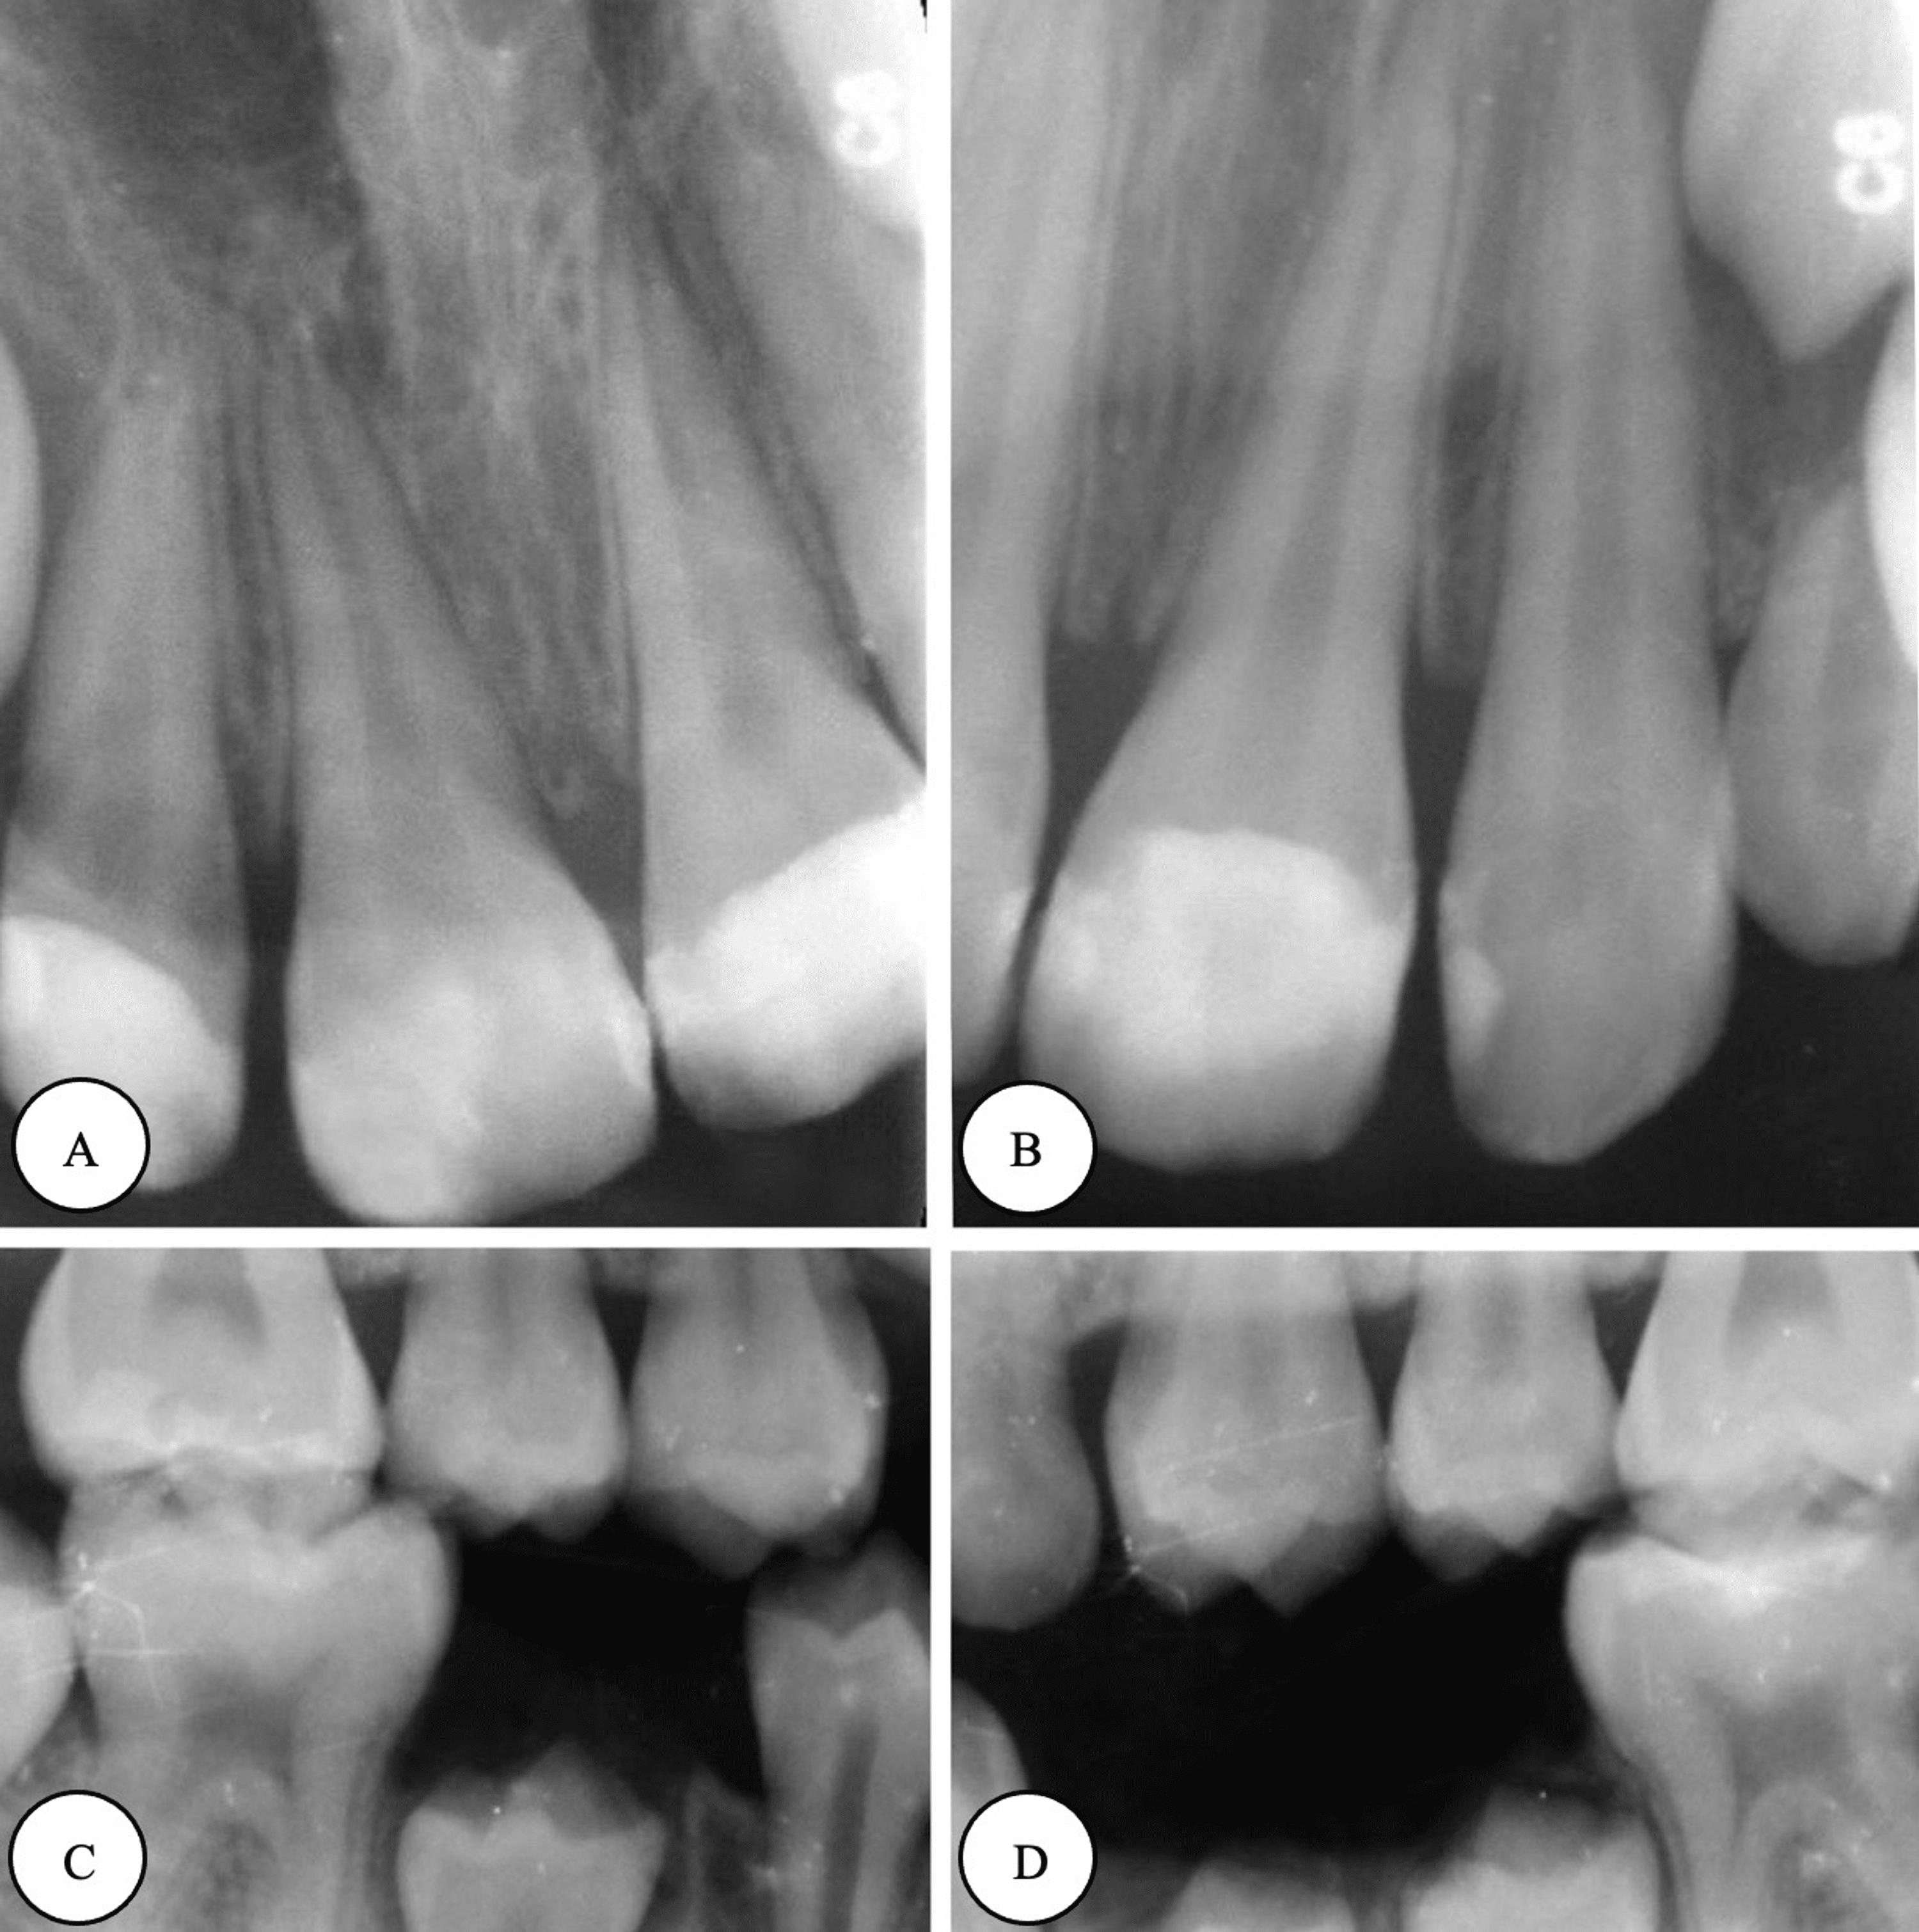

Cureus Comprehensive Dental Management of a Rolandic Epilepsy Patient

Cureus Comprehensive Dental Management of a Rolandic Epilepsy Patient Dental Anesthesia And Epilepsy This article reviews the current knowledge of epilepsy, seizures and antiepileptic drugs and provides guidelines for the management of an acute seizure in the dental office. Poor oral hygiene itself is often also. These patients can be safely managed in a general dental office by an. This paper is a review of the dental management of patients with epilepsy. In. Dental Anesthesia And Epilepsy.

Cureus Comprehensive Dental Management of a Rolandic Epilepsy Patient Dental Anesthesia And Epilepsy In case conscious sedation or general anesthesia is required due to difficult child movements, identifying the severity, frequency,. This paper is a review of the dental management of patients with epilepsy. Epileptic patients have a variety of unique medical and dental needs. These patients can be safely managed in a general dental office by an. This article reviews the current. Dental Anesthesia And Epilepsy.